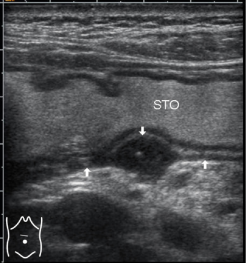

箭头所指为溃疡病灶。左图及中图,超声显示,胃壁局限性增厚,<1.5cm,粘膜面出现凹陷,通过胃镜进一步确定为溃疡灶。